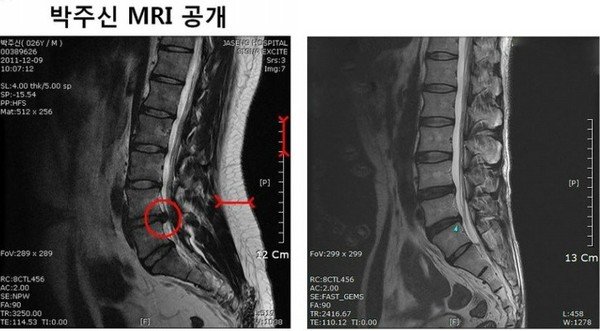

- ▲ 무소속 강용석 의원이 공개한 박원순 시장 아들 박주신의 MRI 사진(좌) 키 173cm 63kg 박주신과 같은 체형을 가진 허리디스크 환자의 MRI 비교. 우측 사진을 보면 허리쪽 지방층이 거의 없다.

6. 박주신 MRI를 확인한 전문의들에 따르면 박씨가 병무청에 제출한 MRI는 최소 90kg 이상 고도비만 환자의 것임. 하지만 박주신은 60kg 초반의 마른 체형임.